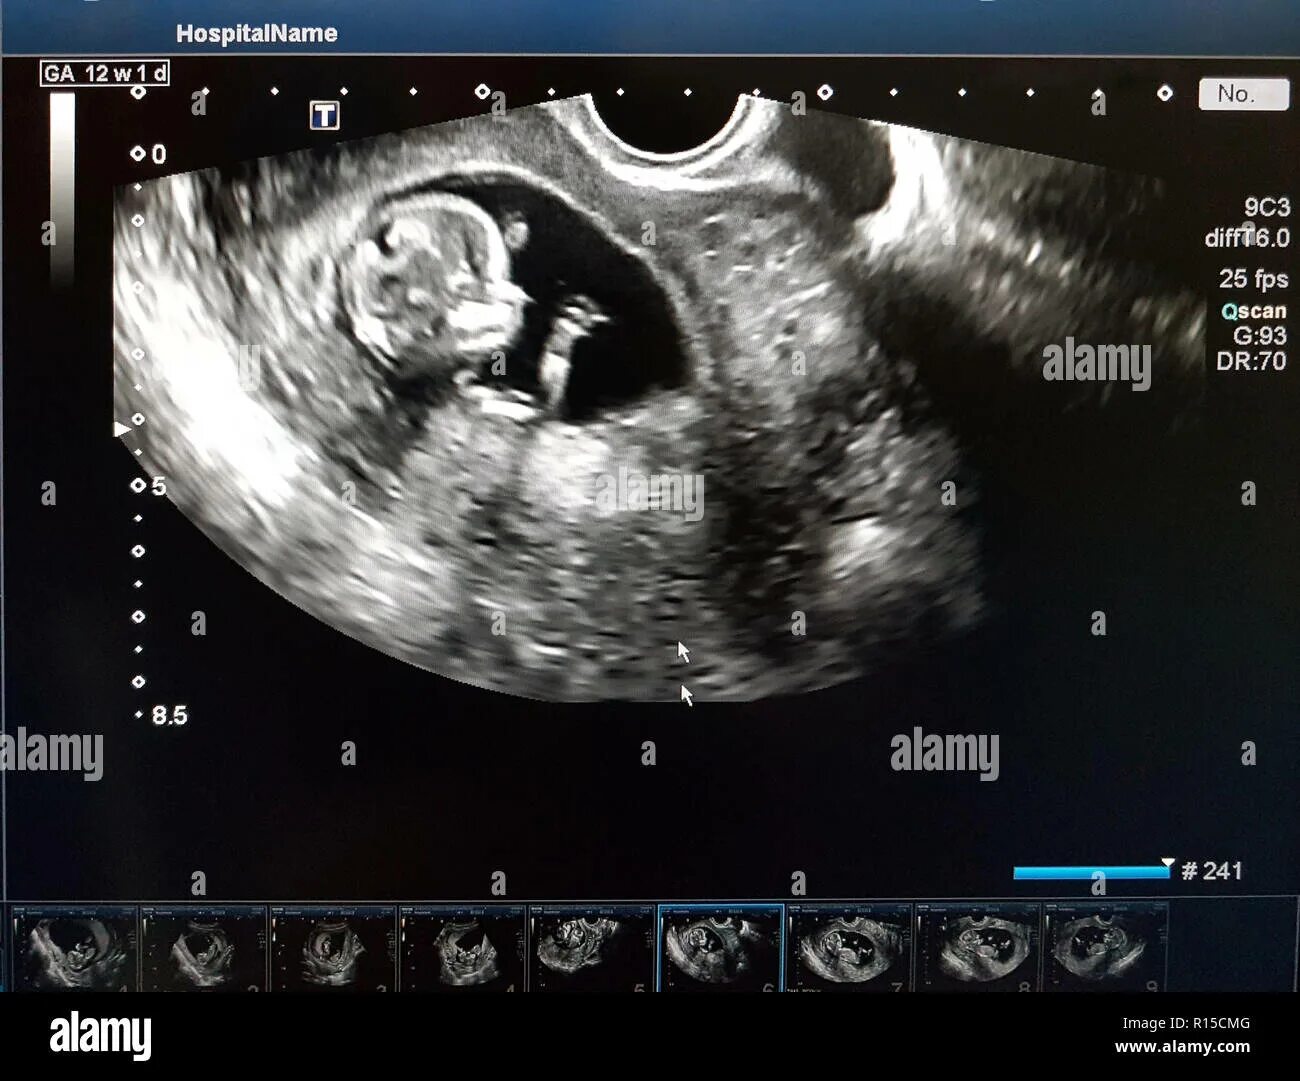

Малыш на первом скрининге